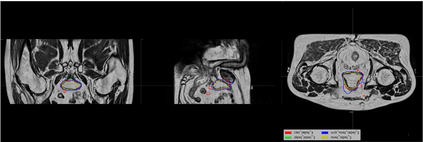

Direct automatic segmentation of objects from 3D medical imaging, such as magnetic resonance (MR) imaging, is challenging as it often involves accurately identifying a number of individual objects with complex geometries within a large volume under investigation. To address these challenges, most deep learning approaches typically enhance their learning capability by substantially increasing the complexity or the number of trainable parameters within their models. Consequently, these models generally require long inference time on standard workstations operating clinical MR systems and are restricted to high-performance computing hardware due to their large memory requirement. Further, to fit 3D dataset through these large models using limited computer memory, trade-off techniques such as patch-wise training are often used which sacrifice the fine-scale geometric information from input images which could be clinically significant for diagnostic purposes. To address these challenges, we present a compact convolutional neural network with a shallow memory footprint to efficiently reduce the number of model parameters required for state-of-art performance. This is critical for practical employment as most clinical environments only have low-end hardware with limited computing power and memory. The proposed network can maintain data integrity by directly processing large full-size 3D input volumes with no patches required and significantly reduces the computational time required for both training and inference. We also propose a novel loss function with extra shape constraint to improve the accuracy for imbalanced classes in 3D MR images.

翻译:3D医学成像的物体,如磁共振成像(MR)成像的直接自动分离,具有挑战性,因为往往需要精确地确定大量调查中大量存在复杂地理不对称的单个物体。为了应对这些挑战,大多数深层学习方法通常会大大提高其模型内可训练参数的复杂性或数量,从而提高其学习能力。因此,这些模型一般需要在运行临床MR系统的标准工作站上花很长的推断时间,并限于高性能的计算机硬件,因为它们的记忆要求很大。此外,要在这些大型模型中安装3D数据集,还要利用有限的计算机记忆,经常使用交换技术,例如补对称培训等,以牺牲从对诊断目的具有临床重要性的投入图像中获得的精细比例的几何地理信息。为了应对这些挑战,我们提出一个具有浅度记忆足迹的银色网络,以有效减少为状态性能所需的模型参数数量。这对于实际就业至关重要,因为大多数临床环境只有低端硬件,计算机功能和记忆有限。拟议的网络可以通过直接处理全尺寸三维化技术来保持数据的完整性,直接处理全尺寸的全尺寸三维的图像,从而大幅改进所需的超度变压的磁度计算。